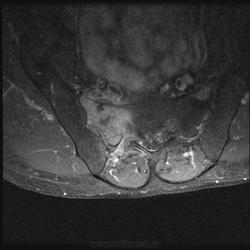

Мужчина, 60 лет. Направлен на МРТ пояснично-крестцового отдела позвоночника для исключения грыжеобразования. Жалуется на боли в правом тазобедренном суставе. Боли начались около месяца назад, сначала проявлялись в виде "неудобства", затем постепенно усиливались. В данный момент при объективном осмотре бережет ногу, хромает. Травмы, воспалительные заболевания отрицает.

При МРТ пояснично-крестцового отдела обратил на себя внимание крестец. Досмотрели крестец с контрастом. Хотелось бы услышать Ваше мнениие по поводу представленных снимков:

А по текущему случаю предложения будут? Не смущает ли кого-нибудь неровный косо-вертикальный гипоинтенсивный сигнал, в особенности заметный на постконтрастных корональных изображениях?